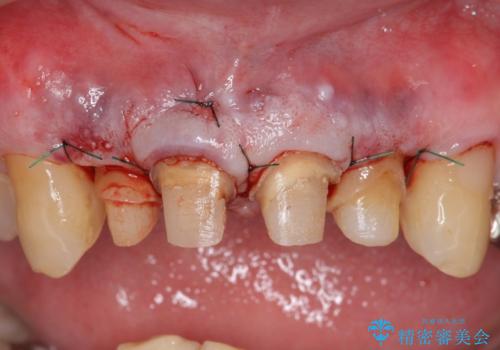

右上2は歯茎のラインを整えるため歯周外科を行っております。

外科処置の注意事項(リスク・副作用など)

- 外科手術のため、術後に出血、痛みや腫れ、違和感を伴います

- 口腔内の状態によっては適応できないことがあります